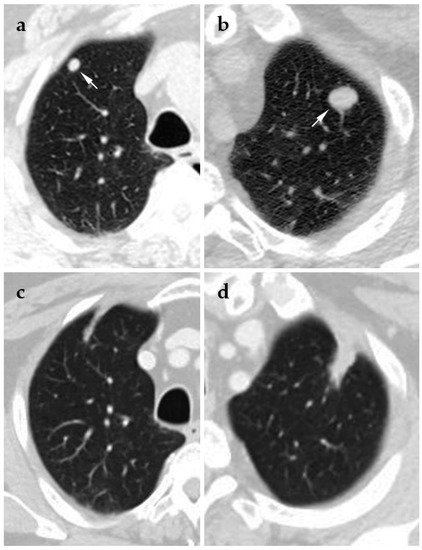

4.3. Microwave Ablation